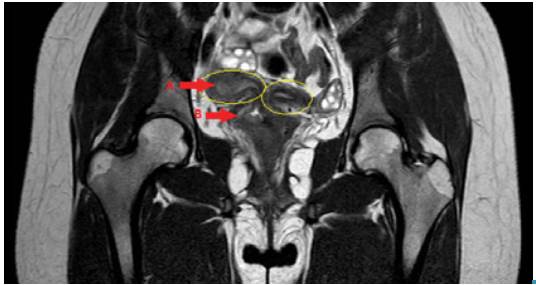

Antibiotic treatment was initiated with clindamycin (600mg every 6 hours) and intravenous gentamicin (240mg every 24 hours) for 7 days. Although dysthermia was not documented during hospital stay, magnetic resonance imaging was performed, revealing uterus didelphys and hematocolpos (Figures 3 and 4).

Magnetic resonance, coronal cut, that shows uterus didelphys, hematopyometra (A), hematocolpos (B) and their respective appendixes.

Figure 3: Magnetic resonance, coronal cut, that shows uterus didelphys, hematopyometra (A), hematocolpos (B) and their respective appendixes.

Source: Document obtained during the study.